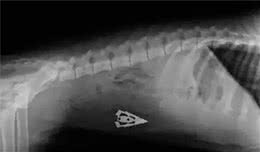

你永远都不会知道一只狗的胃里到底有什么特别是狗狗养久了家长们对于家里的用品收纳管理比较松懈可是真的没有关系吗看看下面X光片照出的东西不明三角物体勺子四驱车玩具刀子鱼钩杂草线团等你想得到的你想不到的狗子无所畏惧、都能吞!